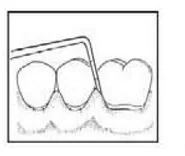

Instrumentem przedstawionym na ilustracji stosowanym w chirurgii stomatologicznej jest